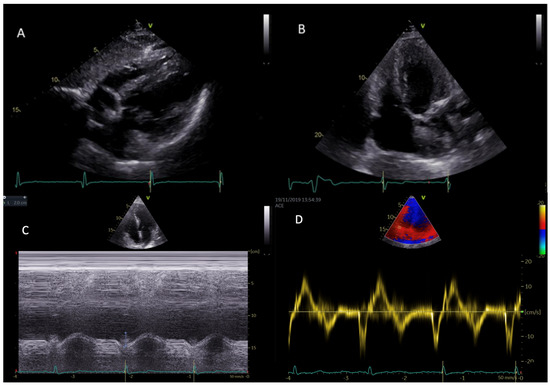

A complete 3D analysis (Figure 2) of the right chambers was performed with the determination of end-diastolic and end-systolic volumes (EDV and ESV) and ejection fraction of the RV (RV EF).

Figure 2.

On the left panel, RV full volume 3D 9-slice; on the right panel, determination of end-diastolic and end-systolic volumes (EDV and ESV) and RV ejection fraction (RV EF) by 3D echocardiographic analysis.